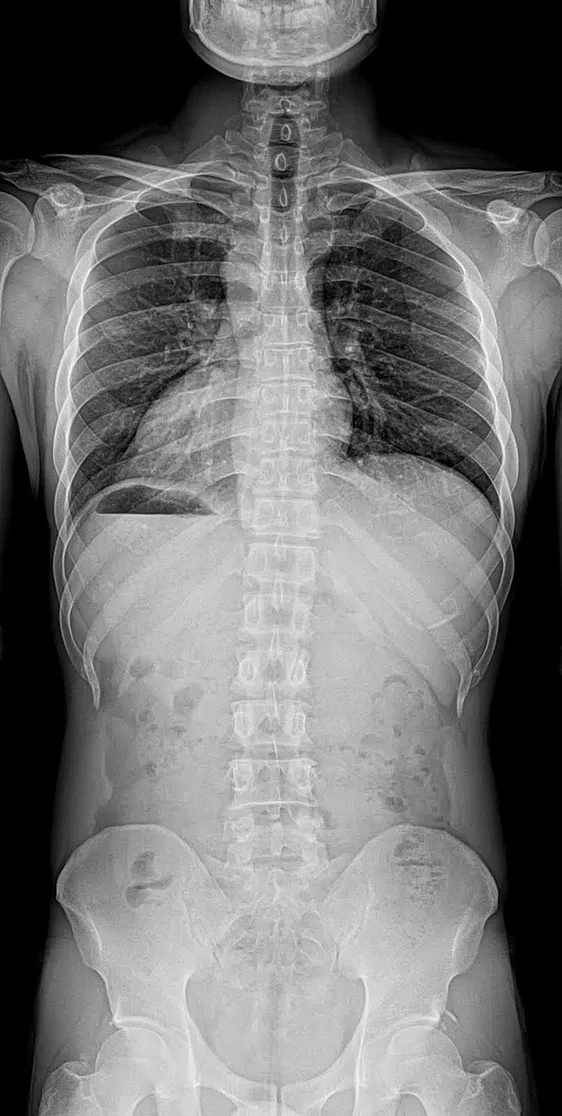

Full spine x-ray

Our digital, high-resolution X-ray services allow our experienced chiropractors to examine your spine and musculoskeletal system with unmatched accuracy. This ensures your treatment plan is:

• Customized to your unique condition

• Safer and more effective

• Data-driven, addressing issues like spinal misalignments, disc problems, or past injuries with confidence